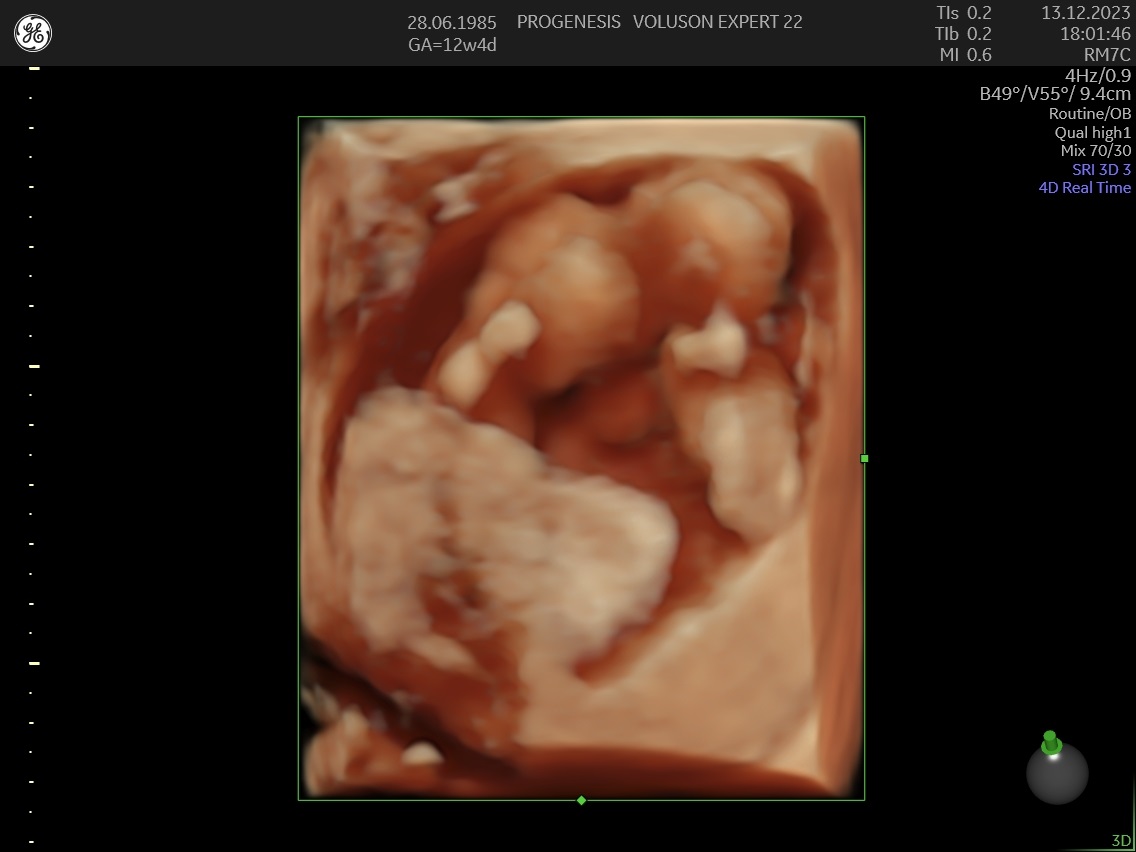

3D/4D LIVE Υπερηχογράφημα

Το 3D/4D LIVE είναι μια νέα τεχνολογία υπερήχων που δημιουργεί εικόνες του εμβρύου σε τρισδιάστατο ή τετραδιάστατο χώρο. Οι εικόνες αυτές είναι πιο ρεαλιστικές από τις παραδοσιακές εικόνες υπερήχων και δίνουν στους γονείς μια πιο ολοκληρωμένη εικόνα του μωρού τους.

Σε πιθανά ανατομικά προβλήματα του εμβρύου μπορούν να βοηθήσουν στην κατανόησή τους από τους γονείς.